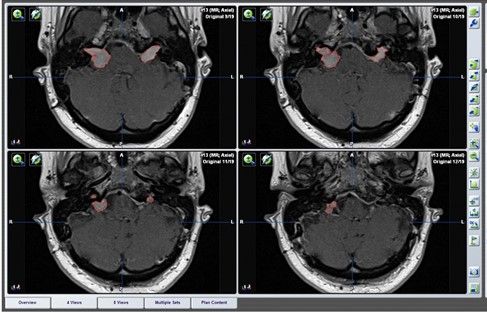

Die Magnetresonanztomographie (MRT) spielt nicht nur in der Diagnosestellung der NF2-Erkrankung eine wichtige Rolle, sondern auch in den langfristigen Kontrollen. Insbesondere zur Überwachung der beidseitigen Vestibularisschwannome (VS) sind regelhafte kranielle MRT-Kontrollen unverzichtbar. Standardmäßig in unserem Zentrum werden daraus die Tumorvolumina mit einer Software (Abbildung 2) kalkuliert. Diese Prozedere ist sehr aufwändig und zeitkonsumierend, aber sehr sensitiv und unverzichtbar um auf Basis dessen auch Therapieindikationen zu stellen und diese zu überwachen (z. B. Operation).

Eine Tumorvolumetrie zur Beurteilung der Vestibularisschwannome ist wichtig zur Einschätzung der Wachstumsdynamik. Diese ist jedoch sehr zeitintensiv. Im Rahmen von wissenschaflichen Projekten mit Industriepartnern sollen anhand von Trainingsdatensätze Deep-Learning Verfahren zur automatisierten Volumetrie beübt und entwickelt werden.